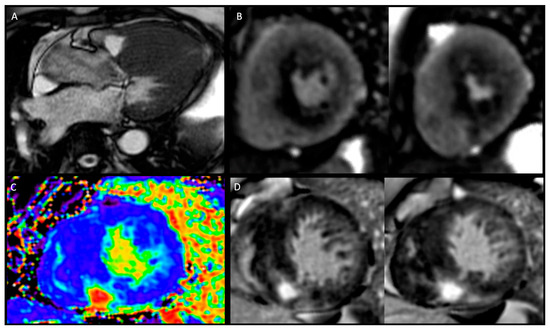

- Athlete’s heart: in response to chronic high-intensity physical activity, the cardiovascular system activates a series of adaptative physiological mechanisms defined as the athlete’s heart, including a constellation of changes with increased biventricular mass, volume, and wall thickness. A stepwise approach to the cardiovascular assessment of athletes is essential to make sense of overlapping clinical phenotypes and eventually provide a correct differential diagnosis between HCM and adaptative cardiac response to exercise. Twelve-lead ECG enhances the sensitivity of the screening process by allowing early detection of cardiovascular conditions distinctively manifesting with ECG abnormalities. Echocardiography has a pivotal role in differentiating physiologic and pathologic responses to exercise, namely athlete’s heart, from HCM. Combining different methods, such as 2D and 3D measurements of cardiac size, volumes, wall thickness, mass index, tissue velocity, and myocardial strain imaging, cardiac ultrasound allows comprehensive morphologic and functional evaluation of the heart and distinction between physiologic and pathologic remodelling. In the presence of abnormal, uncertain, and/or controversial findings from the upstream diagnostic work up, CMR imaging can help distinguish between exercise-induced cardiac remodelling and cardiovascular pathology. CMR represents the current gold standard in the non-invasive assessment of cardiac morphology and quantification of volumes and flow and offers the opportunity for advanced myocardial tissue characterisation with excellent accuracy and precision [24,25].